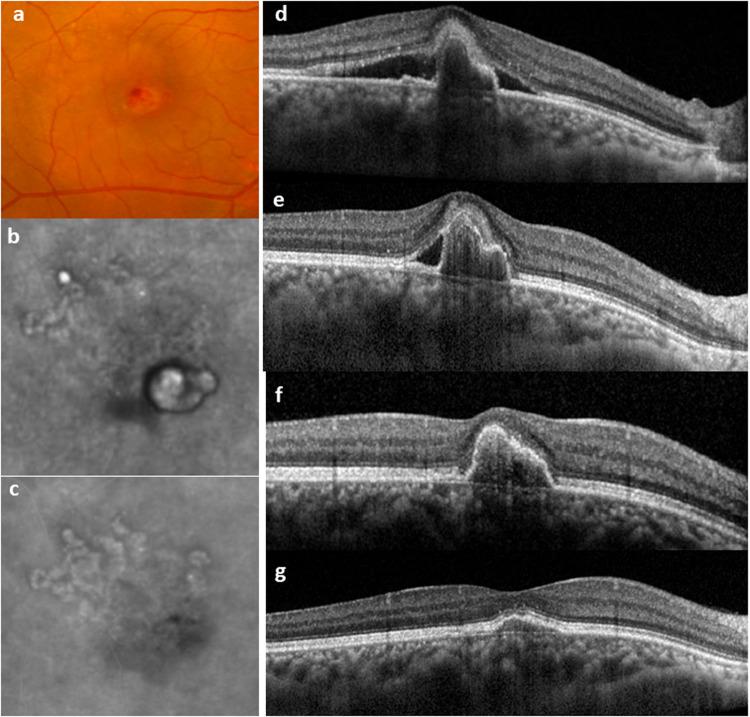

Advances in imaging have led to improved ability to characterize variations in clinical sub-phenotypes of macular neovascularization (MNV) in Age-related macular degeneration (AMD). Polypoidal choroidal vasculopathy (PCV) was initially described based on characteristic features observed in indocyanine green angiography (ICGA) and was thought to be a distinct entity from AMD. However, subsequent careful observations based on confocal scanning laser ophthalmoscopy-based ICGA, optical coherence tomography (OCT) and OCT angiography have led researchers to appreciate similarities between PCV lesion and type 1 MNV in typical neovascular AMD. Concurrently, clinical trials have shown that anti-VEGF monotherapy can achieve favourable visual outcome in the majority of eyes with PCV. These learnings have led to a shift in the way PCV is managed over the past decade. Recent studies have supported the use of non-ICGA based imaging modality to screen for PCV and the adoption of anti-VEGF monotherapy as initial therapy for PCV. A focus of recent research has been in the understanding of the role of choroidal alterations in the pathogenesis of PCV. The concept of pachychoroid in leading to outer retinal ischemia has garnered increasing support. Future research in this area should evaluate the potential of choroidal morphology in guiding personalized therapy in PCV.